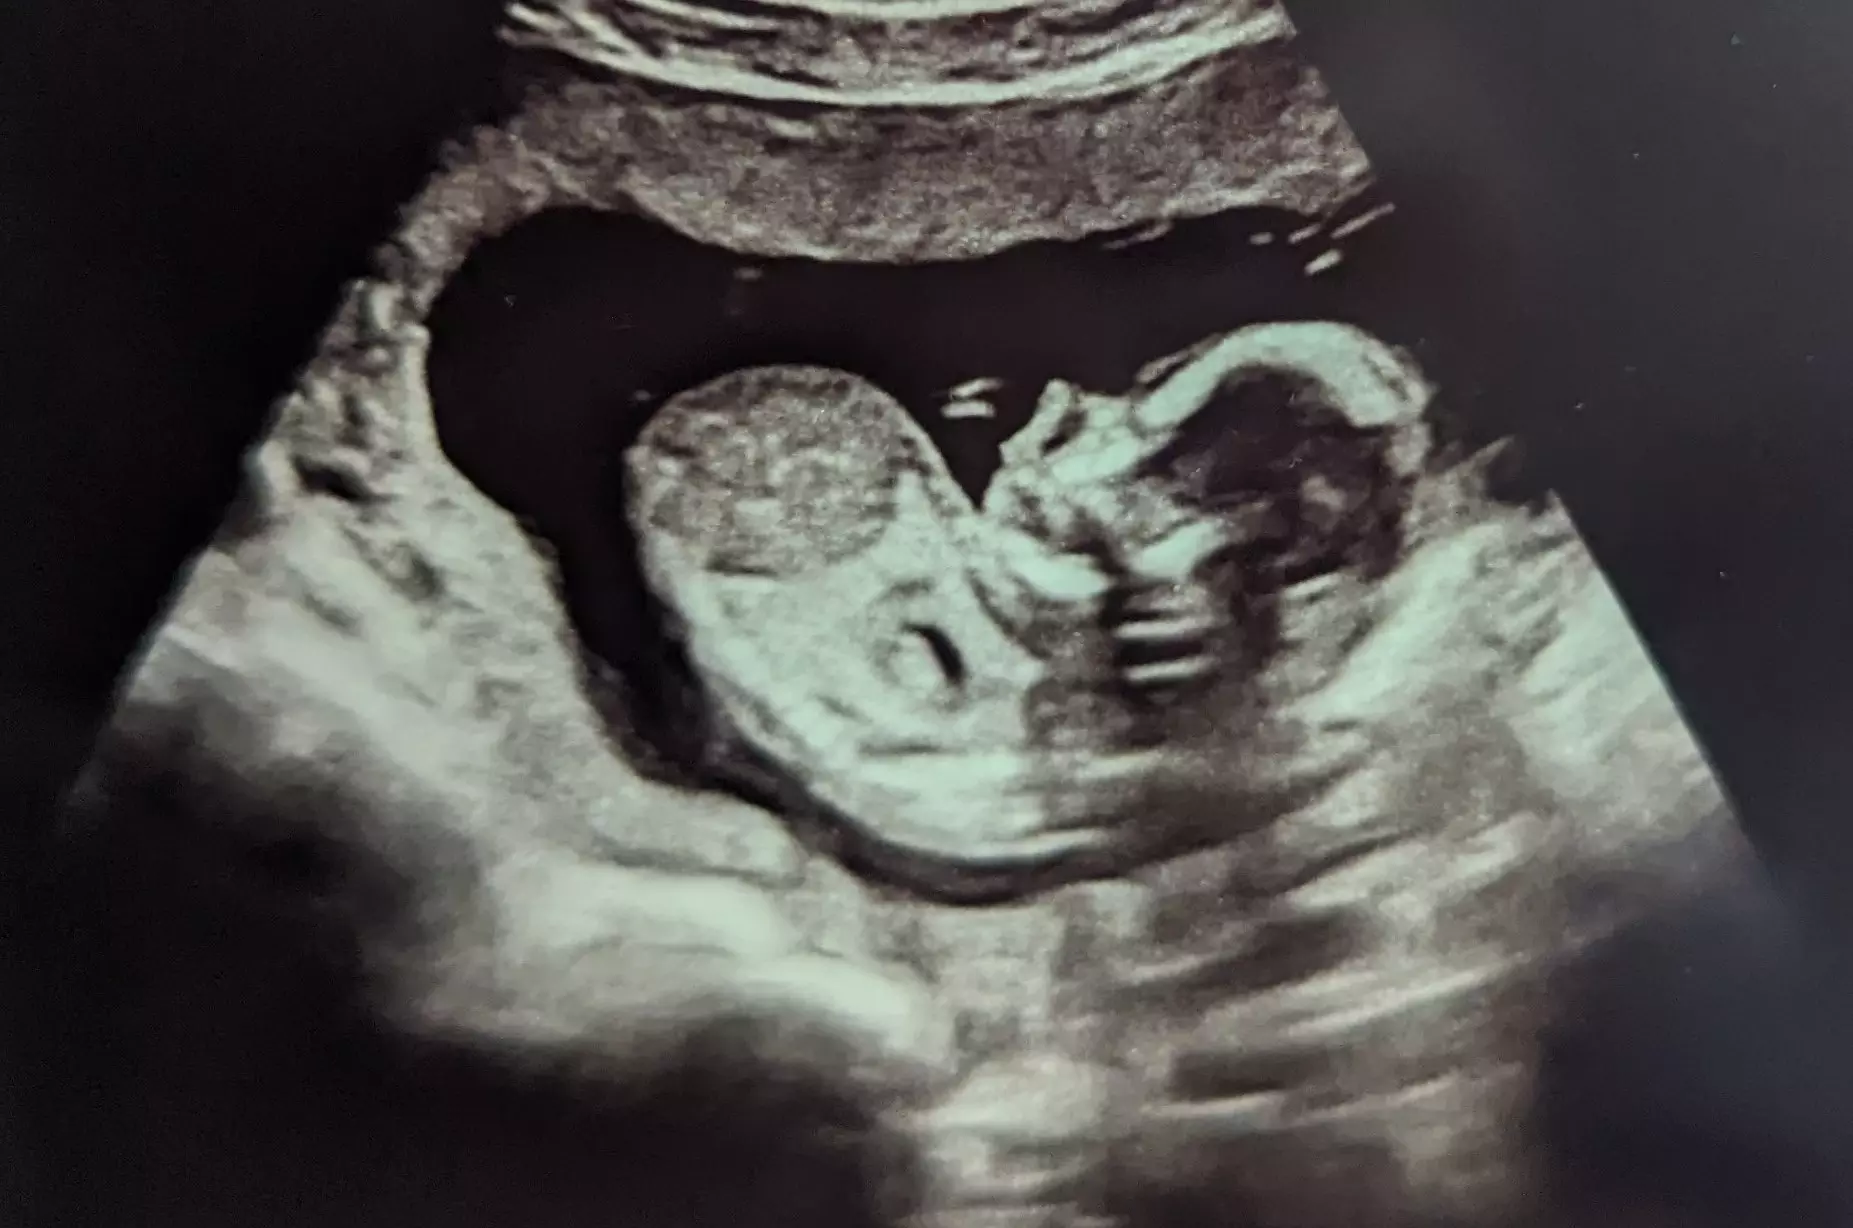

Sarah and the baby’s father have since married, and they are excited to meet their baby boy, Isaiah, due on April 9.

“I'm just so grateful to be pregnant still and carrying this baby boy,” she said. “I know God has a blessing on his life and it's because of the women and staff of the APRN and House of Ruth and other organizations they're partnered with that I'm able to tell this story and welcome my second child into this world with so much love!”